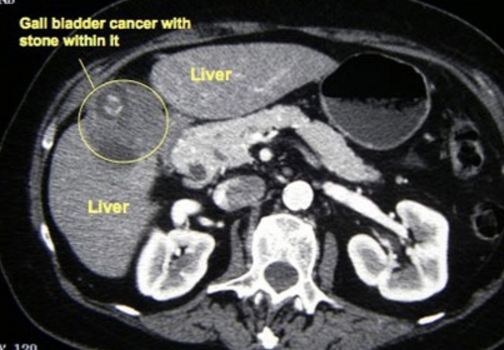

A CT scan showed:

A triphasic CT scan of liver done in July 2015 confirmed:

- Irregular liver surface. Hypodense lesions are seen at both liver lobes, the largest is at segment 7 measures 1.2 cm. These lesions not enhanced in all CT phases.

- Liver cirrhosis with no CT evidence of hepatoma.

- Multiple liver cysts.

- Cholelithlasis.

Fast forward to April 2018 – a repeat Triphasic CT scan showed:

- A solitary non-enchancing homogenous isodense liver nodule 3.3 x 3.6 cm. In view of underlying chronic hepatitis carrier, need to exclude atypical hepatocellular carcinoma.